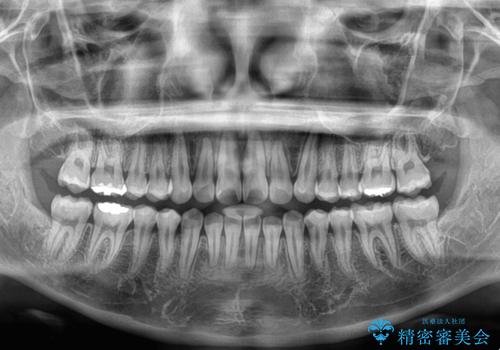

- 上下前歯部のデコボコを気にして来院された患者様です。

叢生は軽度であったため、マウスピースでもワイヤー装置でも対応可能でしたが、マウスピースを長時間使用する自信がないとのことでワイヤー装置にて矯正治療を行うこととしました。

叢生が軽度であったため、僅か半年で装置を除去することができました。